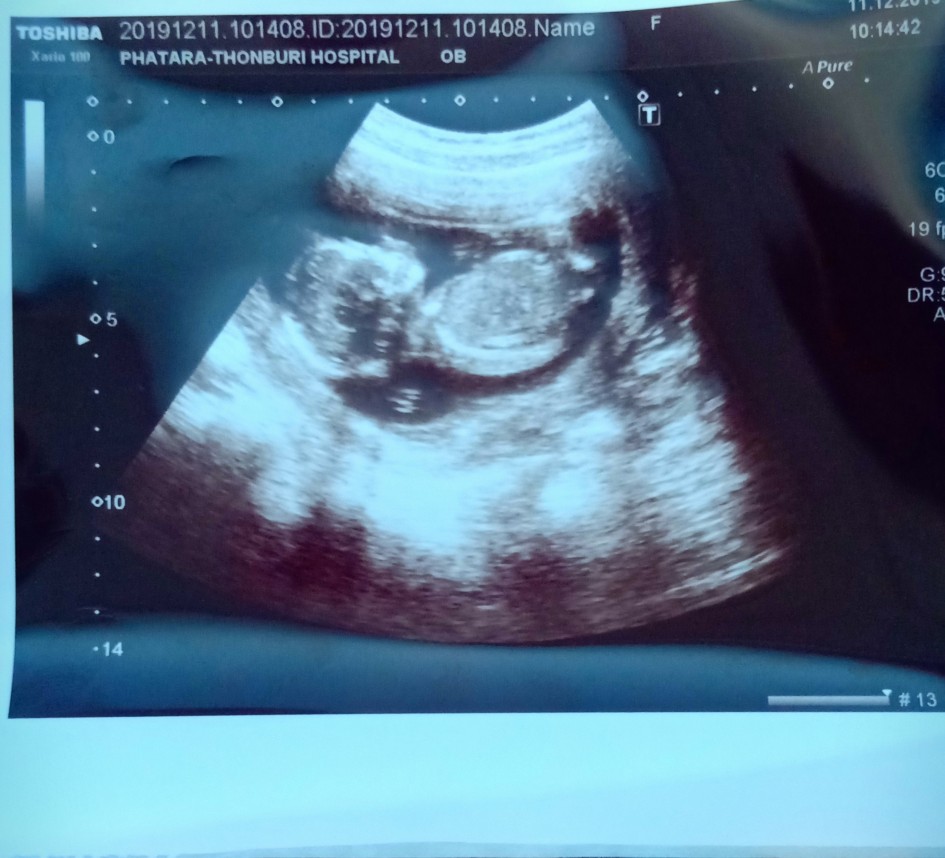

ตอน 15 w จ้าา